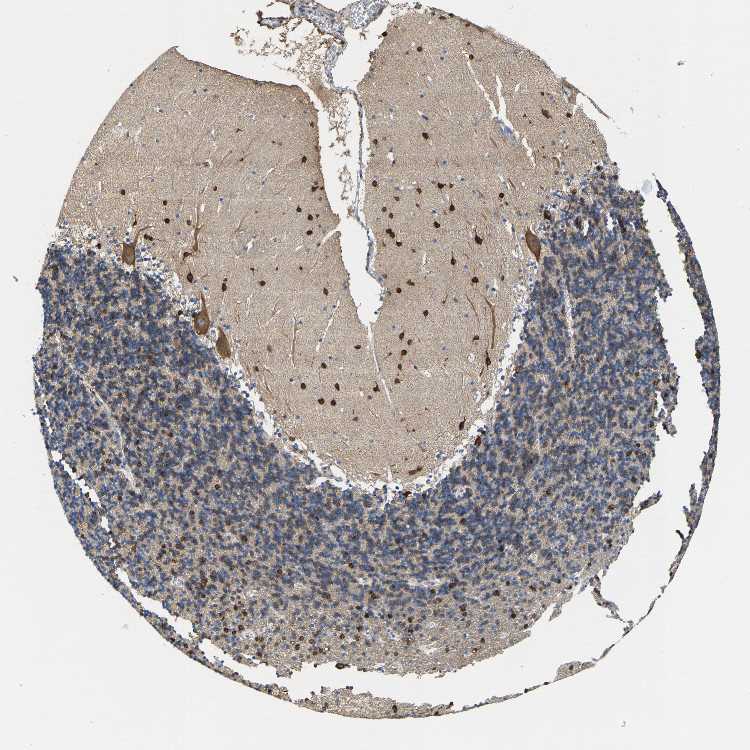

CEREBELLUM - Antibody stainingi

Antibody staining in the annotated cell types in the current human tissue is reported as not detected, low, medium, or high, based on conventional immunohistochemistry profiling in selected tissues. This score is based on the combination of the staining intensity and fraction of stained cells.

Each image is clickable and will lead to virtual microscopy that enables deeper exploration of all samples and also displays staining intensity scores, fraction scores and subcellular localization as well as patient and tissue information for each sample.

Antibody HPA019324

Bergmann glia - cytoplasm/membrane Not detected

Bergmann glia - nucleus Not detected

GLUC cells - cytoplasm/membrane Not detected

GLUC cells - nucleus Not detected

Purkinje cells - cytoplasm/membrane Medium

Purkinje cells - dendrites Medium

Purkinje cells - nucleus Not detected

Granular cells - cytoplasm/membrane High

Granular cells - nucleus Not detected

Molecular layer - neuropil Not detected

Molecular layer cells - cytoplasm/membrane High

Molecular layer cells - nucleus Not detected

Processes in granular layer Not detected

Processes in molecular layer Not detected

Processes in white matter Not detected

Synaptic glomeruli - capsule Not detected

Synaptic glomeruli - core Not detected

White matter cells - cytoplasm/membrane Not detected

White matter cells - nucleus Not detected